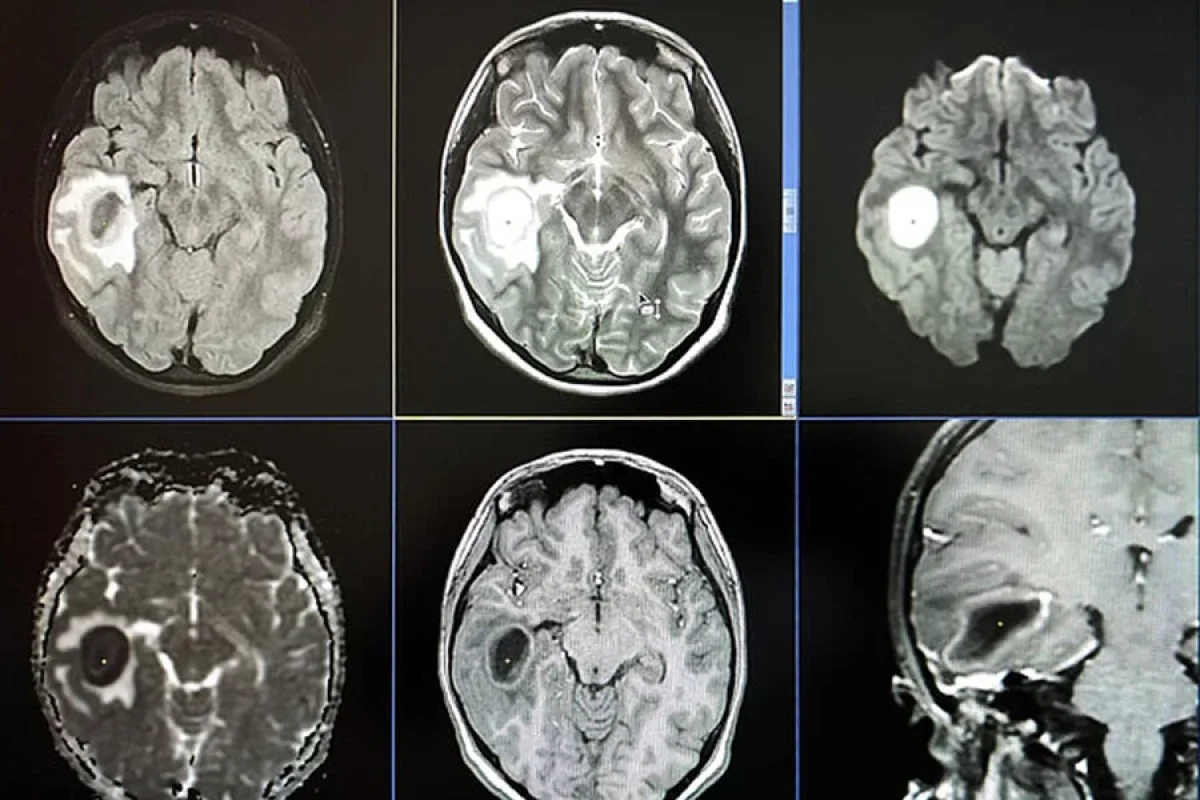

Onun müalicəsi müsbət nəticə vermədiyindən xəstə qıza MRT təyin olunub. Qızın beynində irin aşkar olunub.